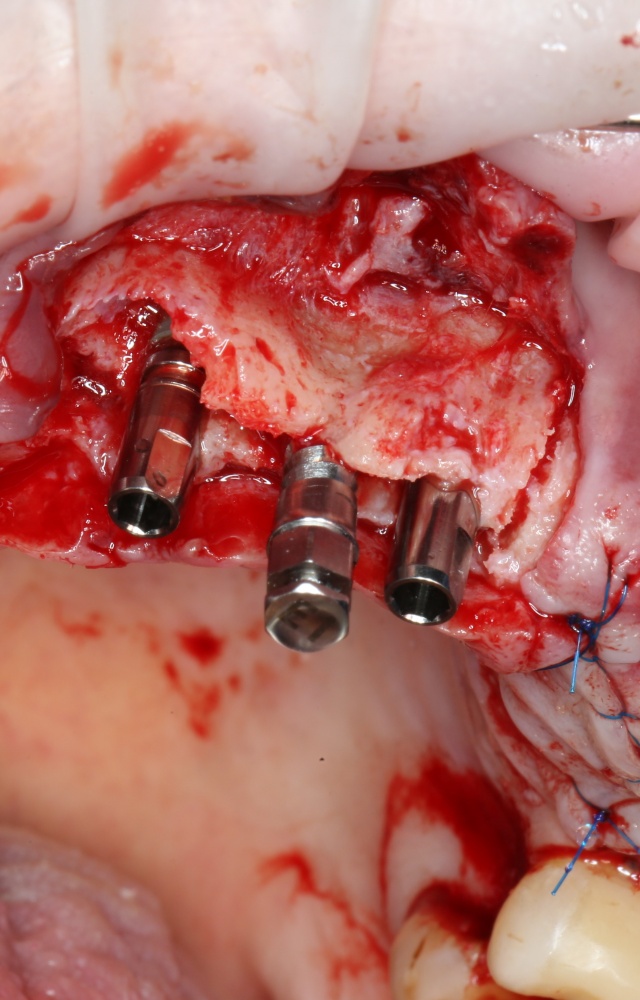

Откроем область операции и посмотрим, что там:

Вроде как, всё неплохо. Наверное, можно поставить имплантаты?

ну, или как-то так:

При этом, я хотел бы обратить ваше внимание на один важный момент. То, с чем вы сейчас работаете — не кость, в привычном нам гистолого-физиологическом понимании. Это костная мозоль вперемежку с графтом. Её свойства довольно сильно отличаются от того, что мы привыкли называть костной тканью. Поэтому при установке имплантатов соблюдайте максимальную осторожность и щадящий режим. Никаких диких торков, усилий, больших переходов между размерами фрез допускать нельзя. Будьте аккуратны.